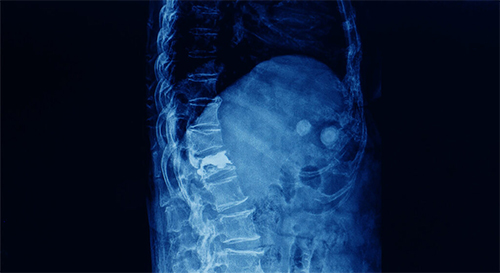

Non-vascular interventions are advanced minimally invasive procedures performed under imaging guidance such as ultrasound, CT scan, or fluoroscopy. These procedures allow specialists to accurately diagnose and treat a wide range of medical conditions affecting organs and tissues without the need for traditional open surgery.

By using small needles, catheters, or probes inserted through the skin, doctors can reach the targeted area with high precision. This approach significantly reduces surgical trauma, lowers the risk of complications, and shortens hospital stay. Most patients experience quicker recovery, minimal pain, and can return to their normal daily activities much sooner compared to conventional surgical methods.

Non-vascular interventional procedures are widely used in the management of tumors, infections, fluid collections, and organ blockages. These techniques have become an essential part of modern medical care due to their safety, effectiveness, and ability to treat complex conditions with minimal disruption to surrounding healthy tissues.